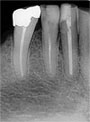

With a state-of-the-art digital radiography system, we can take your digital X-rays with significantly less radiation exposure than traditional X-ray imaging systems. This system also enables our patients to see their X-rays within seconds on their chairside monitor.